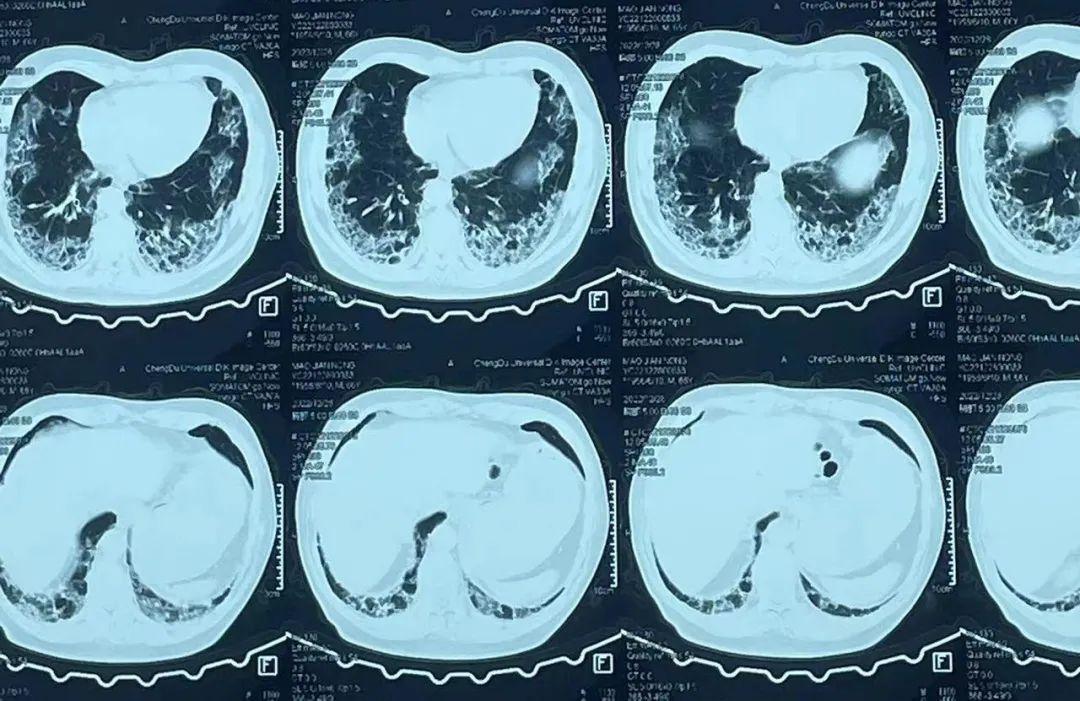

什么是“白肺”?

白肺,一般是指在X光或者CT检查下,肺部显影呈一片白色。主要由肺部细菌感染或人体炎症反应所致。

但并不是肺部只要出现了炎症就都叫白肺,一般来讲肺部炎症较重、渗出液较多,白色的影像区域面积达到70%一80%时,才把它称为白肺。

而且白肺并不一定是新冠造成的,此外,还有和新冠病毒无关的其他病毒导致的肺部感染,比如呼吸道合胞病毒、流感病毒。